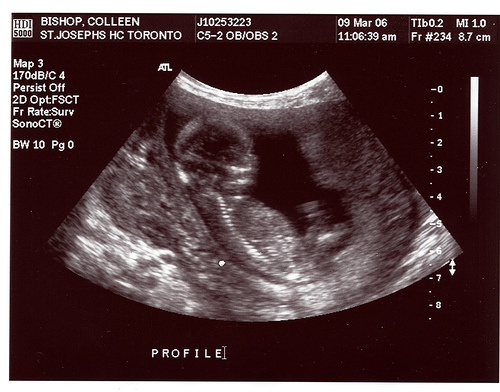

Ушки плода подтягиваются выше, к тому месту, где и должны быть у малыша. Подбородок и нос становятся четче. Лицо приобретает индивидуальные черты. И на УЗИ уже можно уловить сходство малыша с кем-нибудь из родителей.

УЗИ на 13-й неделе беременности